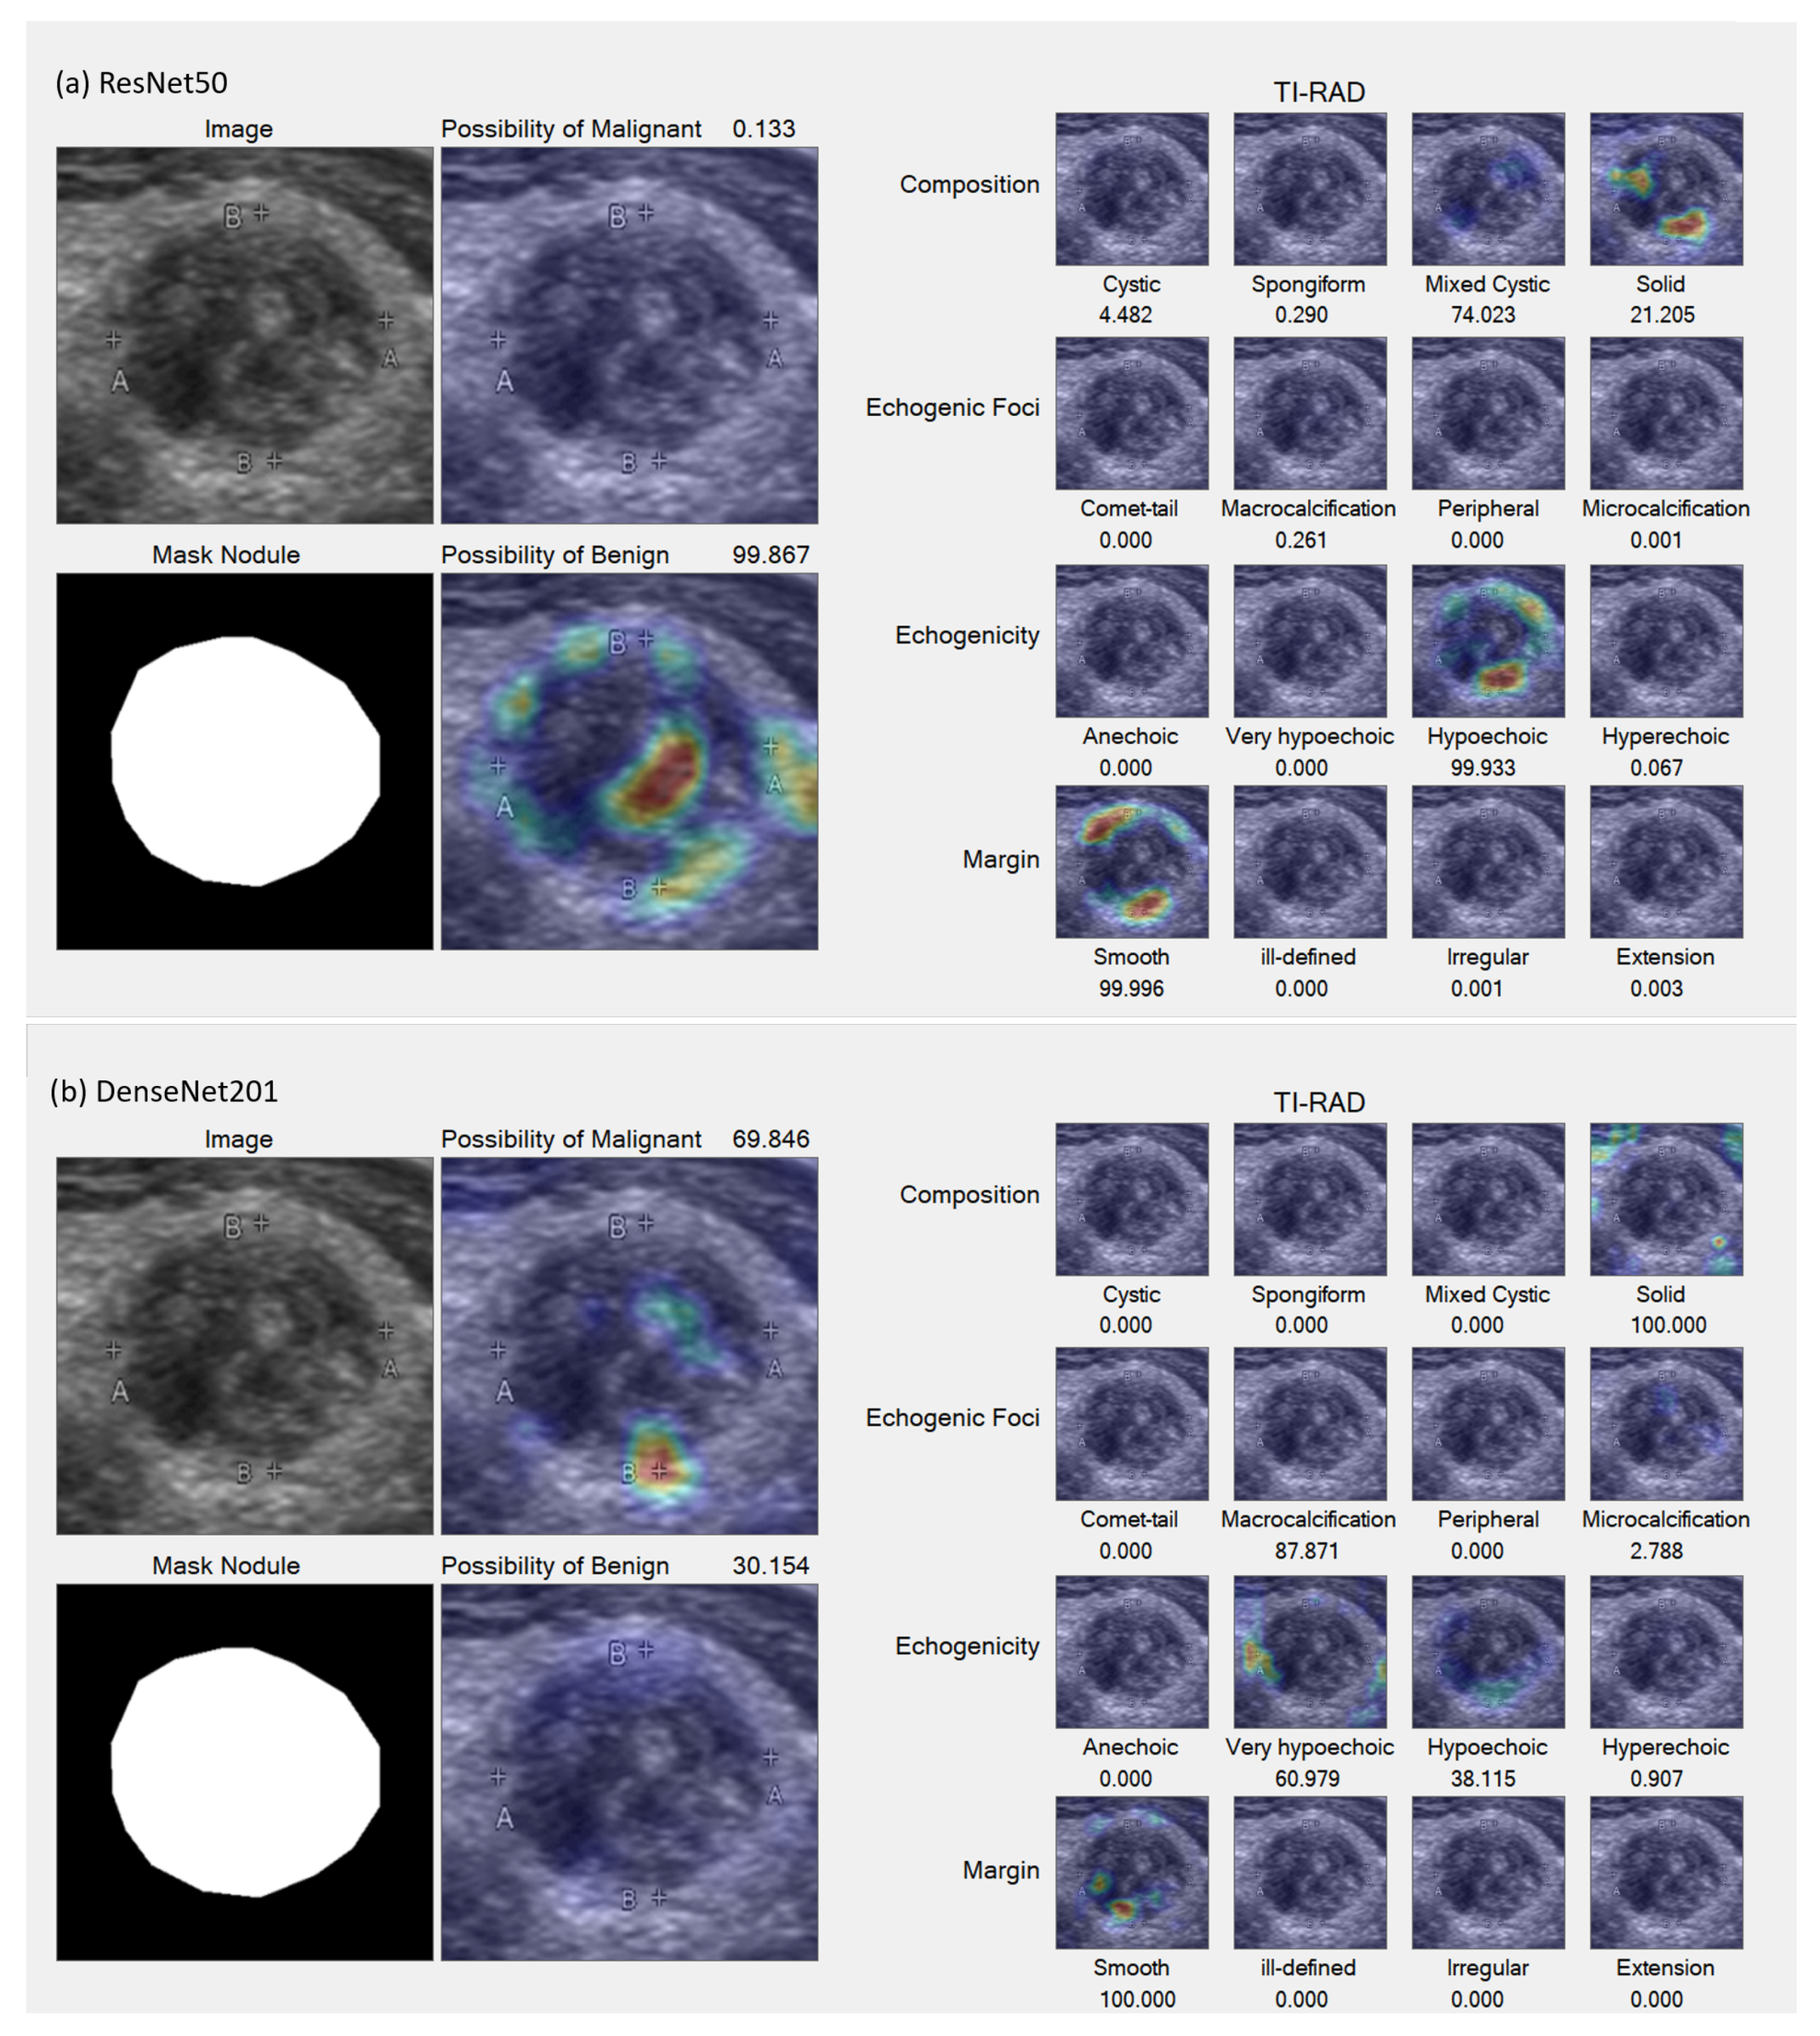

In the Grad-CAM visualization, we conducted individual analyses for each classification and sought the expertise of expert radiologists (coauthors DS and SB) to interpret the results.

Figure 7 and

Figure 8 present sample accurate outcomes along with corresponding expert explanations, while

Figure 9 displays a sample incorrect outcome and the experts’ interpretations for those cases.

Figure 7.

Samples of accurate results. (a,b) Benign lesion exhibiting well-defined mixed solid–cystic composition, classified under TI-RADS-2, thereby denoting a low suspicion for malignancy (1.5%). Both ResNet50 (a) and DenseNet201 (b) models accurately identified mixed solid–cystic components, the hyperechoic solid region, and the smooth border, all of which contributed to a high likelihood of a benign diagnosis.

Figure 7.

Samples of accurate results. (a,b) Benign lesion exhibiting well-defined mixed solid–cystic composition, classified under TI-RADS-2, thereby denoting a low suspicion for malignancy (1.5%). Both ResNet50 (a) and DenseNet201 (b) models accurately identified mixed solid–cystic components, the hyperechoic solid region, and the smooth border, all of which contributed to a high likelihood of a benign diagnosis.

Figure 9.

Sample incorrect result. (a,b) Malignant lesion characterized by a well-defined iso to very hypoechoic solid composition and internal micro-calcifications, classified as TI-RADS-5, indicating a high suspicion for malignancy (35%). The ResNet50 model (a) incorrectly suggested a higher likelihood of benignity, failing to detect the very hypoechoic component, in contrast to the DenseNet201 model (b), which indicated a greater possibility of malignancy by successfully identifying this component. Nevertheless, both models were unable to detect the internal punctate echogenic foci.

Figure 9.

Sample incorrect result. (a,b) Malignant lesion characterized by a well-defined iso to very hypoechoic solid composition and internal micro-calcifications, classified as TI-RADS-5, indicating a high suspicion for malignancy (35%). The ResNet50 model (a) incorrectly suggested a higher likelihood of benignity, failing to detect the very hypoechoic component, in contrast to the DenseNet201 model (b), which indicated a greater possibility of malignancy by successfully identifying this component. Nevertheless, both models were unable to detect the internal punctate echogenic foci.